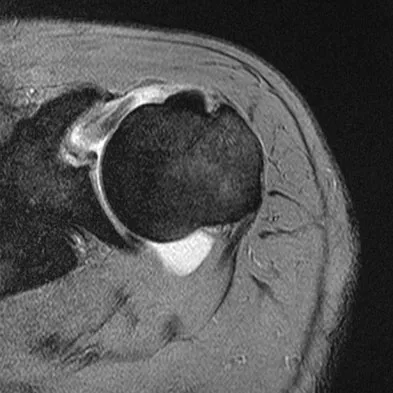

A 72-year-old woman who is right hand-dominant has severe pain in the right shoulder that has failed to respond to nonsurgical management. She reports night pain and significant disability. Examination reveals 30 degrees of active forward elevation. An AP radiograph is shown in Figure 27. Which of the following treatment options will provide the best functional improvement?

Explanation

The patient has end-stage rotator cuff tear arthropathy. The radiograph shows complete proximal humeral migration (acromiohumeral interval of 0 mm), severe glenohumeral arthritis, and acetabularization of the acromion. In addition, she has "pseudoparalysis" with active elevation of only 30 degrees. Reverse shoulder arthroplasty affords her the best opportunity for pain relief and functional improvement. The other procedures have mixed results but typically are better for pain relief than they are for functional gains. Frankle M, Siegal S, Pupello D, et al: The reverse shoulder prosthesis for glenohumeral arthritis associated with severe rotator cuff deficiency: A minimum two-year follow-up study of sixty patients. J Bone Joint Surg Am 2005;87:1697-1705.

References:

- Werner CM, Steinmann PA, Gilbart M, et al: Treatment of painful pseudoparesis due to irreparable rotator cuff dysfunction with the Delta III reverse-ball-and-socket total shoulder prosthesis. J Bone Joint Surg Am 2005;87:1476-1486.